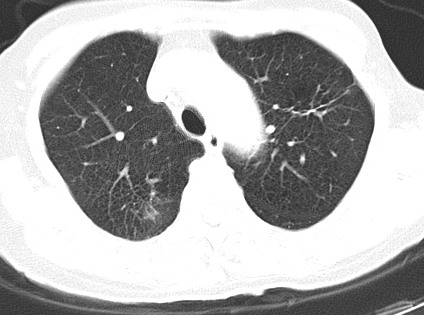

以下是引用hhcckk在2007-3-2 14:51:00的发言:[br]考虑结核球可能性大,依据[br]1病灶在下叶背段,结核的好发部位[br]2病灶内有大量的钙化,纵隔内有大量的淋巴结钙化[br]3重要的是半年前与现在相比无变化,假如是肿瘤的话不会这么‘善良’[br]4病灶周围卫星灶不明显,病灶有毛刺,胸膜凹陷,肿瘤不能完全排除,有条件的话最好做个活检

以下是引用liuyue在2007-3-2 17:15:00的发言:[br]1位置:右上叶后段[br]2性质:大分叶、粗长毛刺、条状斑片状钙化、纵隔多发淋巴结钙化,无强化,故考虑:肺结核灶(陈旧)